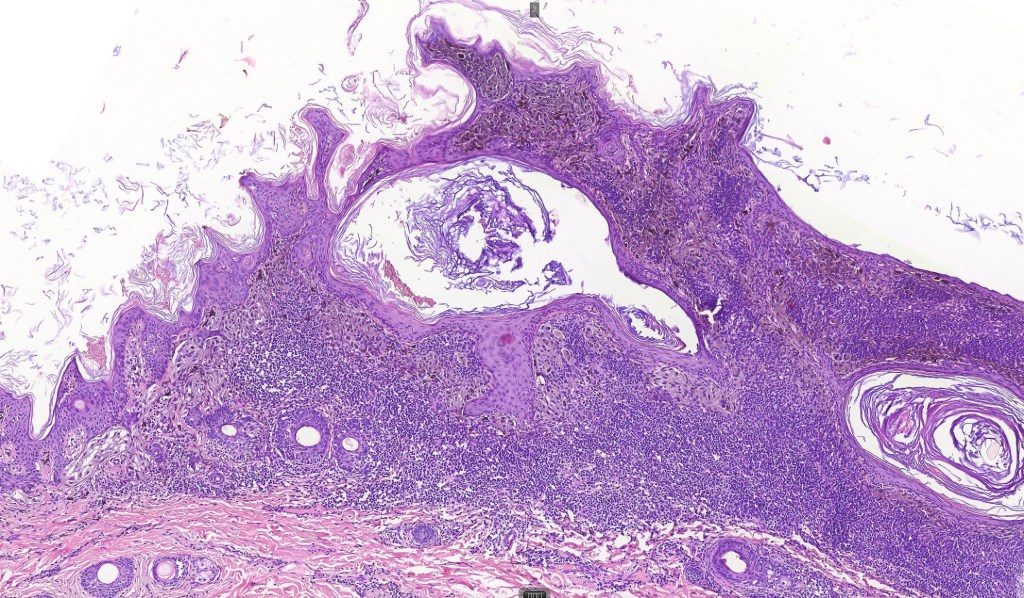

Although most scalp nevi can be readily classified into the regular nevus subtypes- common, congenital, blue etc, exceptionally they may show features more commonly seen at “the socalled milk-line” sites. Some authors use the term “atypical nevus of the scalp”.

Histological features

•Junctional/compound

•Large dyscohesive nests with retraction artifact, not restricted to the tips of the epidermal ridges

•Heavy pigmentation (sometimes gray/green)

•Bridging common, often over multiple rete ridges

•Variable atypia (can be marked)

•Central pagetoid spread

•Superficial dermal atypia

•Junctional mitoses sometimes present, dermal mitoses+/-, can be multiple but never atypical

•Dermal fibrosis (sometimes lamellar)

. HMB45 shows gradation with depth, Ki67 is low